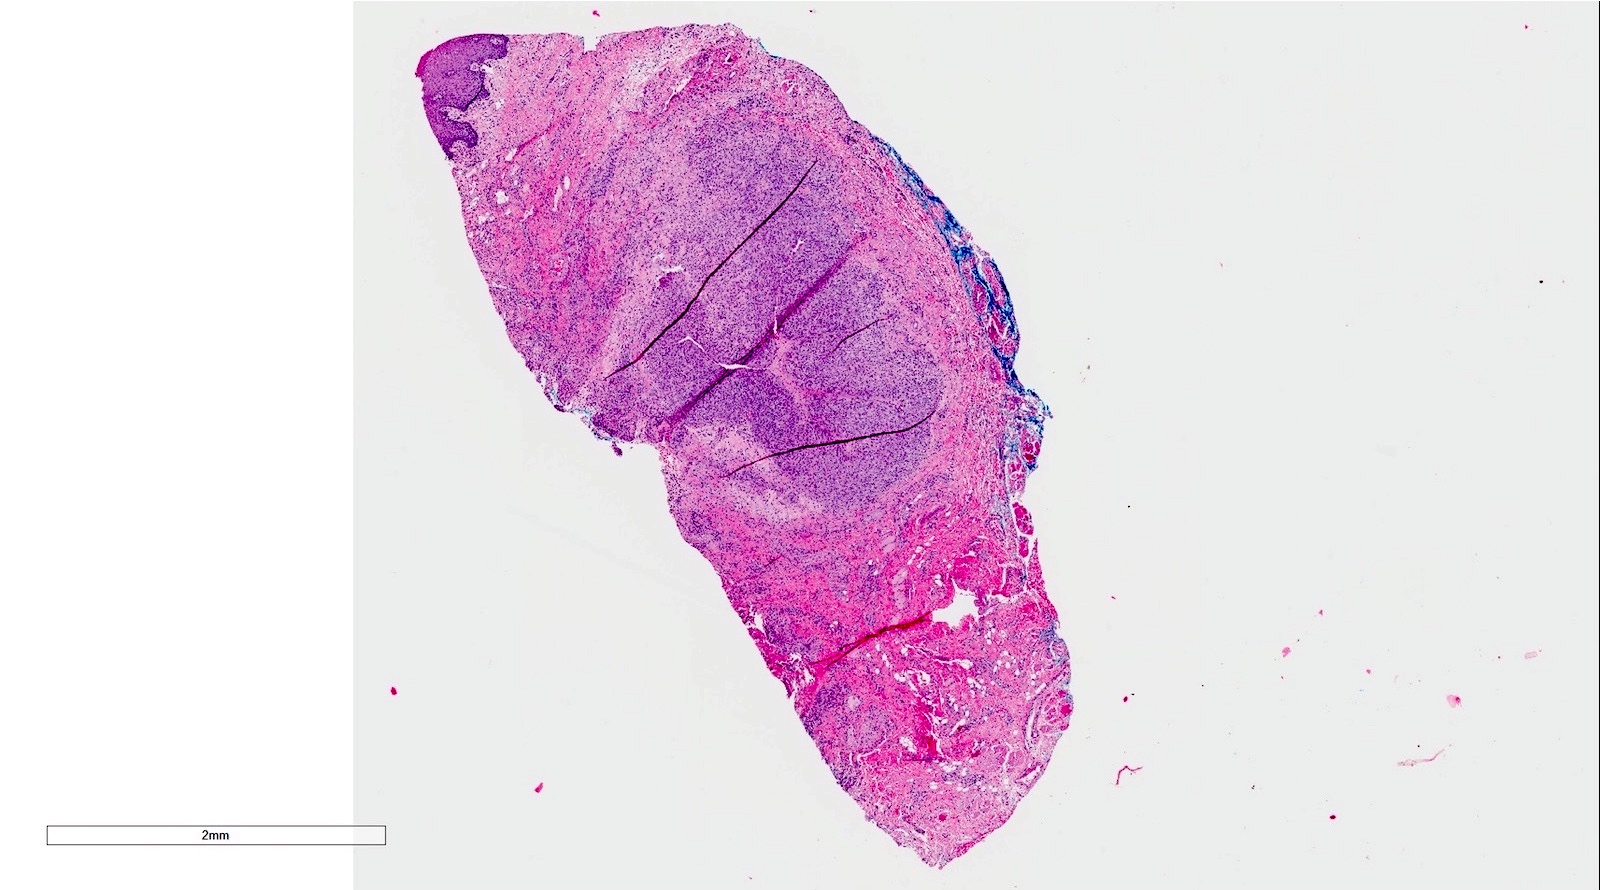

Microscopic (histologic) description

- If removed intact

- Pseudocyst cavity containing mucin, abundant epithelioid foamy histiocytes (muciphages), neutrophils and granulation tissue (Acta Histochem 2014;116:40)

- Removed salivary gland parenchyma showing obstructive changes

- Acinar atrophy, ductal dilatation with periductal hyalinization, interstitial lymphoplasmacytic infiltrate and interstitial fibrosis at late stage (J Oral Maxillofac Surg 2008;66:2050)

- May see ruptured feeding salivary duct with squamous metaplasia (J Oral Maxillofac Surg 2008;66:2050)

- Long standing lesions organize into fibrosis resembling a fibroepithelial polyp (Acta Histochem 2014;116:40)

- No epithelial cyst lining, may see overlying surface oral mucosa with variable atrophy in superficial mucoceles (J Oral Maxillofac Surg 2011;69:1086)

Microscopic (histologic) images